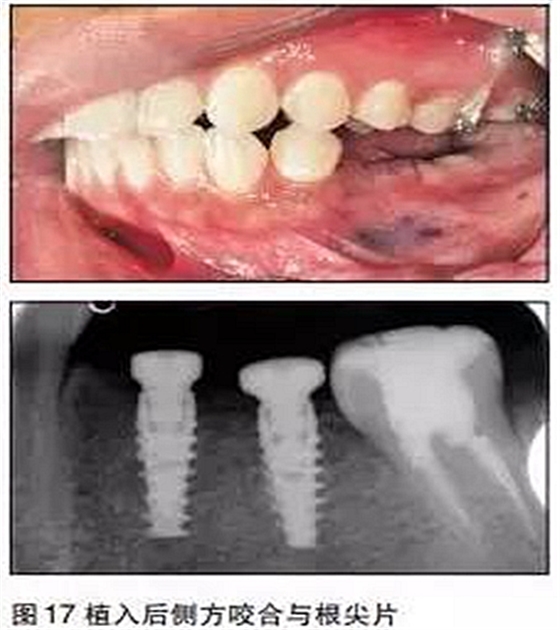

③用骨鑿去除部分牙槽嵴頂骨質(zhì),球鉆定位,逐級備洞,植入2枚NobelActivie4.3×10mm種植體,植體植入初期穩(wěn)定性35N;

④上愈合基臺,一期縫合。

三個(gè)月后

采用閉口印模法取模,比色,送技工中心制作。

口內(nèi)就位

最后修復(fù)體在口內(nèi)就位,35N鎖緊螺絲,封閉螺絲口,納米樹脂充填螺絲開口,調(diào)牙合,拋光完成。